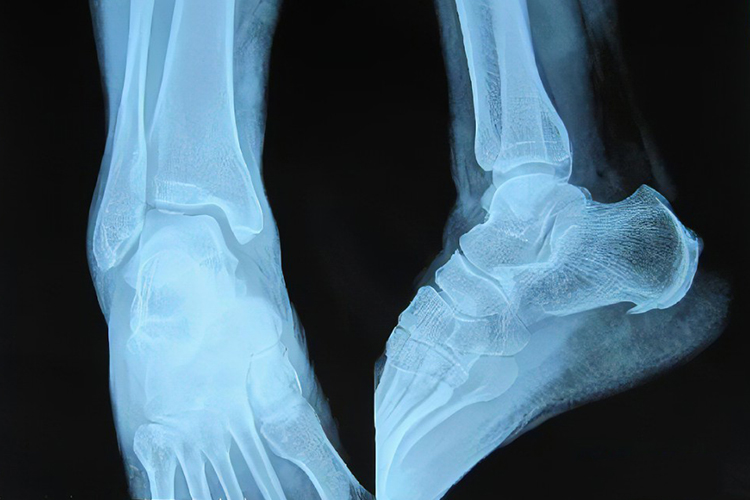

脚后跟骨刺临床指跟骨骨质增生,若骨质增生小,多无明显症状,若骨质增生偏大可触及隆起,局部肿胀、活动受限。

脚后跟骨刺临床指跟骨骨质增生,病变较小时通常无明显肿胀,若跟骨骨质增生较大时,可触及骨性隆起,表现为局部肿胀、活动受限。该病的典型症状为跟骨疼痛,晨起后站立或久坐起身站立时疼痛剧烈。